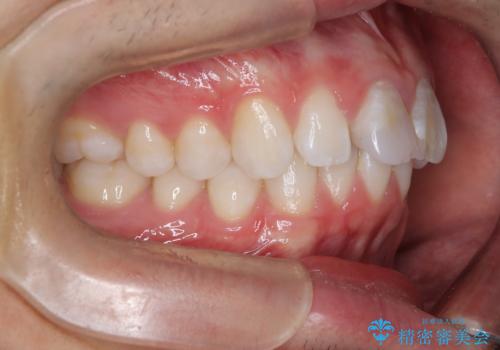

【ワイヤー矯正 11ヵ月で矯正終了!】歯のでこぼこを治したい!

- 「歯のでこぼこを治したい 1年くらいで矯正を終わらせたい」を主訴に来院された患者様です。

叢生量は多く無く歯の傾斜も標準傾斜だったので歯は抜かずにワイヤー矯正で治療を行いました。

左側は2級傾向が強く臼歯の遠心移動をご提案しましたが、1年以内に矯正を終わらせたいという患者様のご意向で希望されず叢生を改善する矯正となりました。